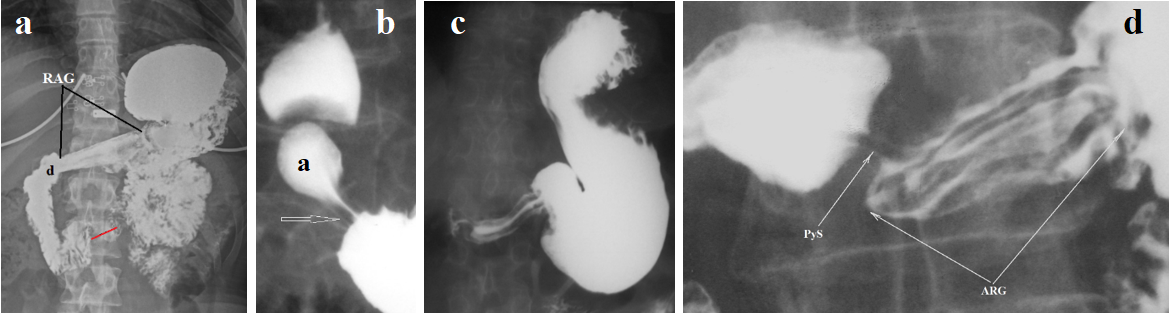

Diagnosis of GERD

The presence of heartburn supports the diagnosis of GERD. Gastroscopy reveals only reflux complications: erosion, ulcers, peptic stenosis, and Barrett's disease. Dilation of intercellular spaces was the most consistently reported histologic change in the esophageal mucosa of patients with nonerosive reflux disease, being observed in 41%-100% of patients and 0%-30% of controls. The mean intercellular space width was at least 2 times greater in patients than in controls, irrespective of esophageal acid exposure. Leukocytes and eosinophils participate in the inflammatory process [12]. Chandrasoma et al., believe that the appearance of cardiac epithelium over the lower esophageal sphincter (LES) occurs due to cardiac metaplasia of the squamous epithelium due to exposure to gastric juice. Thus, cranial displacement of the squamo-columnar junction (SCJ) is indicative of GERD. In the early stages of development, acid damaged only the intra-abdominal portion of the LES. In such cases, it does not yet enter the esophagus and cannot be detected by pH monitoring. This also implies that physiological reflux is an error in using pH monitoring. They also showed that acid exposure to the intra-abdominal portion of the LES leads to its damage. The LES opens, resulting in shortening of its functional portion [13]. X-ray examination with increased gastric pressure reveals shortening of the LES relative to the age norm, dilation of the esophagus, to a greater extent above the LES, i.e., in the phrenic ampulla [8]. (Figure 1).

Figure 1. Radiographs of the esophagus and esophagogastric junction taken during high pressure in the stomach. (a) In a patient with mild GERD, the LES is contracted during abdominal compression. Its true length between the two blue dots is 2.4 cm. (The true height of D-10 is 2 cm). (b) A patient with a long history of GERD and non-esophageal symptoms. The LES length is 0.7 cm. Symmetrical narrowing of the esophagus at the level of the aortic arch (aorto-esophageal sphincter - AES) was the cause of the non-esophageal symptoms. (c) Wide esophageal ampulla and narrow esophagus with longitudinal and transverse folds. Between the ampulla and the esophagus, a narrowing at the site of the proximal sphincter - Schatzki ring (SR) is determined. The combination of reflux esophagitis with a narrow esophagus and SR is suggestive of EoE. (d-e) EoE with a narrow lumen and rigid esophageal wall. A small ampulla indicates GERD. To create high pressure, it is closed by a contracted proximal sphincter (PS) and injects barium into the stomach.